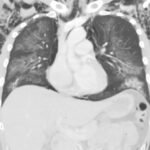

Electronic cigarette (e-cigarette) or vaping associated lung injury (EVALI) cases have increased with the popularity of e-cigarettes in the mostly young, healthy population. Some common symptoms associated with EVALI include shortness of breath and chest pain, and the most common diagnostic imaging findings are organizing pneumonia and diffuse alveolar damage seen on computed tomography (CT). Pneumomediastinum is a known sequela of EVALI.1 In the setting of pneumomediastinum in EVALI, EVALI is a diagnosis of exclusion, so other sources of pneumomediastinum need to be evaluated. EVALI has diverse presentations, and this case is a unique representation of a disease process that is becoming more commonplace with the increase in popularity of vaping. It is important to be aware of the clinical symptoms of EVALI, which can be nonspecific and can include gastrointestinal symptoms along with respiratory symptoms. It is equally important to recognize the diverse image findings of EVALI, which can include subcutaneous emphysema and pneumomediastinum. In this case, pneumomediastinum is seen in EVALI, and the patient was successfully treated with empiric antibiotic coverage, steroids, and conservative measures—making sure to limit any coughing or increases in intrathoracic pressure that can cause worsening of pneumomediastinum.